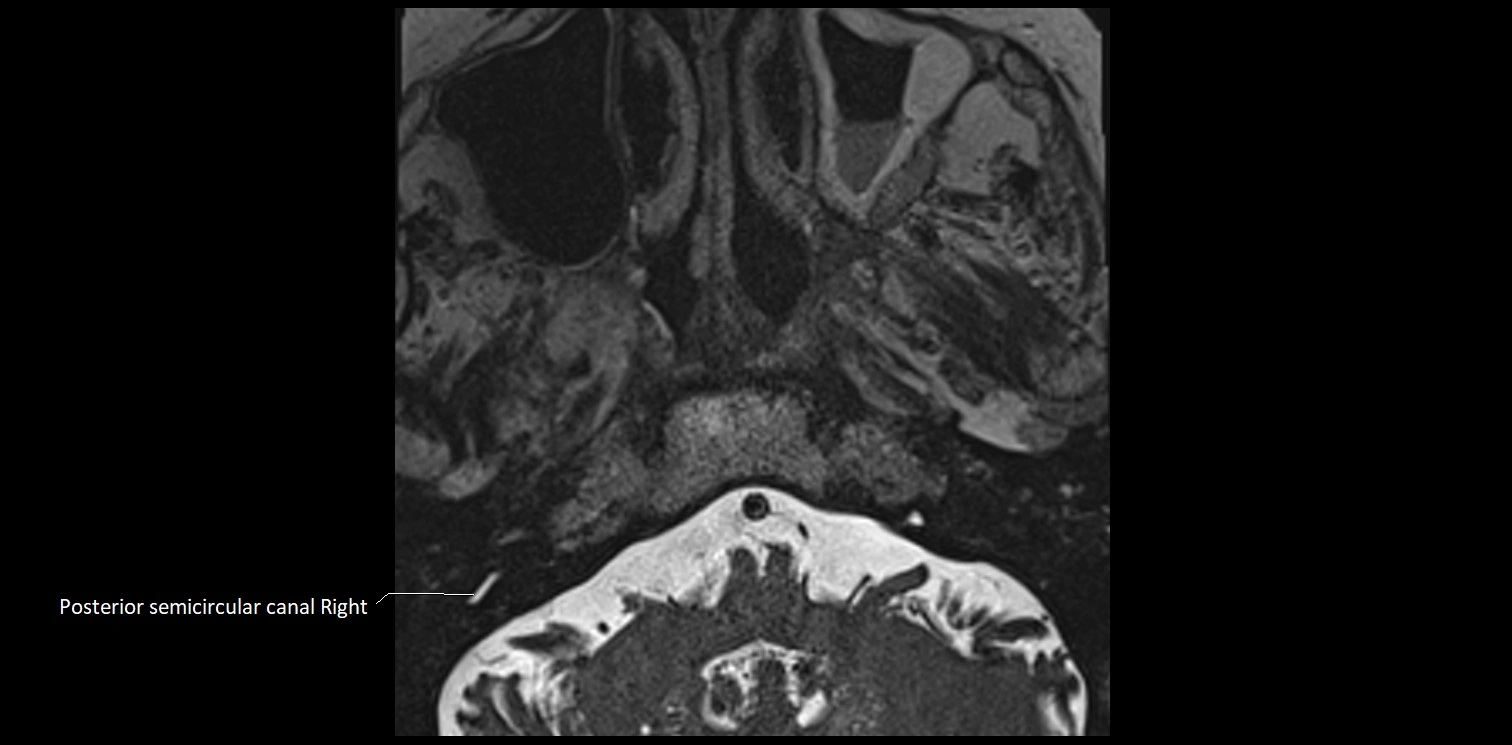

MRI images

image